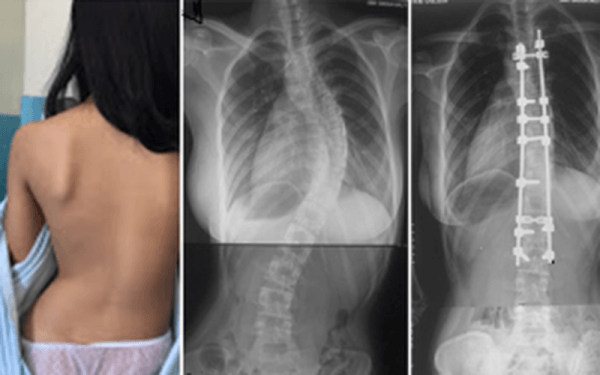

Trật khớp háng bẩm sinh có thể gây gù, vẹo cột sống ở trẻ do tình trạng bất cân xứng của chi dưới. (ảnh minh họa)

- Gây gù, vẹo cột sống do tình trạng bất cân xứng của chi dưới.